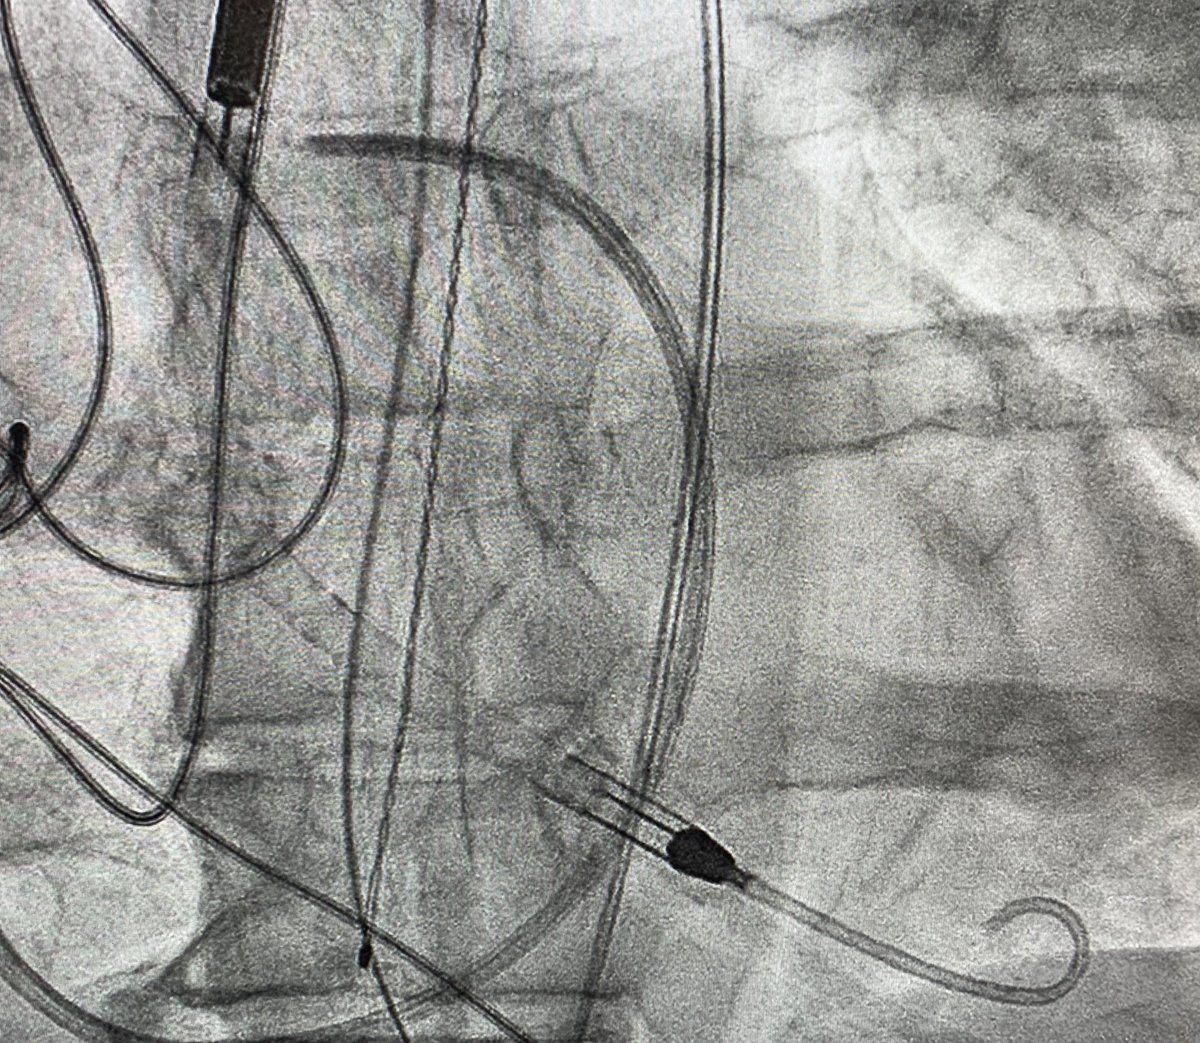

4/7 Quick single-access (a la @jason_wollmuth et al) run-off angiogram at the very end confirming distal flow before removing peel-away sheath (or can perform via Radial access) to assess need for antegrade perfusion catheter...

5/7 Remove peel-away sheath. Cinch Perclose around leave-in sheath. Suture sheath in at appropriate angle (after shallow initial access [cantalever principle a la @J_M_McCabe]) and with sutures placed cranially to preserve forward sheath momentum...

6/7 Place dressings. Reassess Hemodynamics (check response to device: especially effect on RV, need for escalation). Recheck device position/remove slack. Place A-Line. Only then up to CICU....